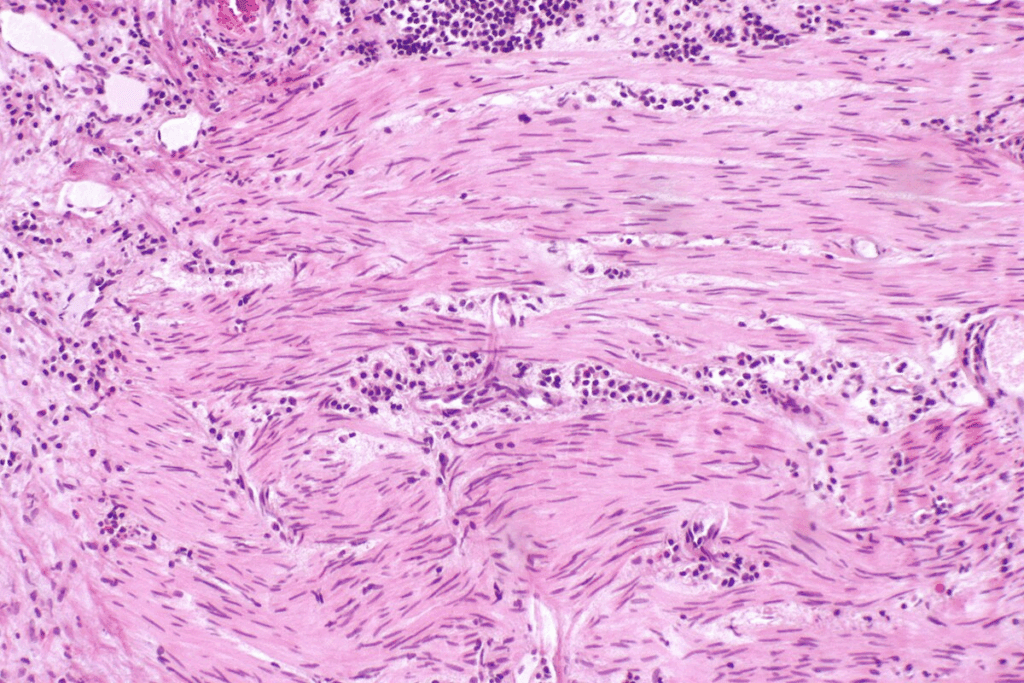

Grading of Bladder Cancer Tumors

Bladder cancer tumors are also graded based on how much they look like normal cells. The grade shows how fast the cancer is likely to grow and spread. Tumors are usually classified as low grade or high grade. Low-grade tumors grow and spread slowly, while high-grade tumors are more aggressive.

Tumor Size, Grade, and Location

The size, grade, and location of the tumor are key in bladder cancer prognosis. Bigger tumors or those with higher grades (more abnormal cells) usually have a worse prognosis. Tumors in certain bladder areas can also be harder to treat.